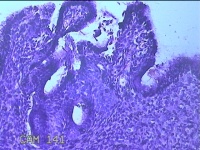

宫颈赘生物

性别

女

年龄

49岁

临床诊断

人乳头瘤病毒感染

一般病史

宫颈HPV阳性TCTLSLL

标本名称

大体所见

灰白粉红色肿物1.2x0.8x0.2cm两个,表面光滑。

图2